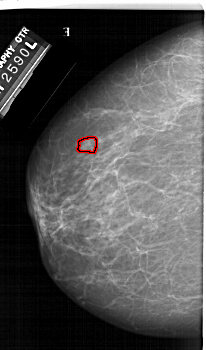

FILE: A_1423_1.LEFT_CC.OVERLAY

TOTAL_ABNORMALITIES 1

ABNORMALITY 1

LESION_TYPE MASS SHAPE LOBULATED MARGINS CIRCUMSCRIBED

ASSESSMENT 4

SUBTLETY 3

PATHOLOGY BENIGN

TOTAL_OUTLINES 1

BOUNDARY